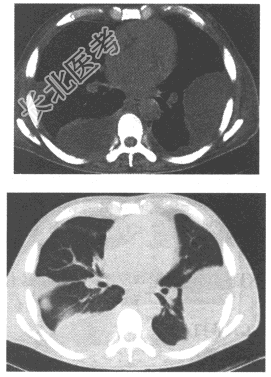

- 单项选择题某前列腺癌患者治疗后复查胸部CT如下图所示,则应诊断为

A、胸膜间皮瘤

B、胸膜增厚

C、胸腔少量积液

D、液气胸

E、胸腔包裹性积液